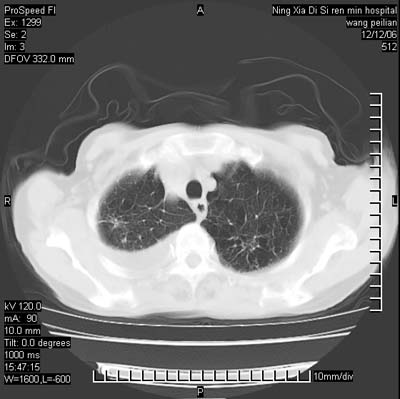

标题: CT5609:胸部:女77 病史不详 [打印本页]

标题: CT5609:胸部:女77 病史不详

两肺可见多个大小不等的结节,左侧有胸水,纵隔淋巴结增大,考虑是细支气管肺泡癌

两肺尖纤维索状影,两下肺结节块状影,且有钙化灶,右胸腔积液。考虑肺结核并胸膜炎。

两肺尖纤维索状影,两下肺结节块状影,且有钙化灶,右胸腔积液。考虑肺结核并胸膜炎肺间质纤维化

两肺以间质性病变为主,并有胸腔积液,考虑结核

考虑:1、慢性支气管炎合并全小叶型肺气肿、间质纤维化;

2、双肺结核;

3、右侧胸膜炎(积液)。

双肺见多个结节状及条索状影,双侧胸腔积液,右侧叶间积液,考虑结核性胸膜炎